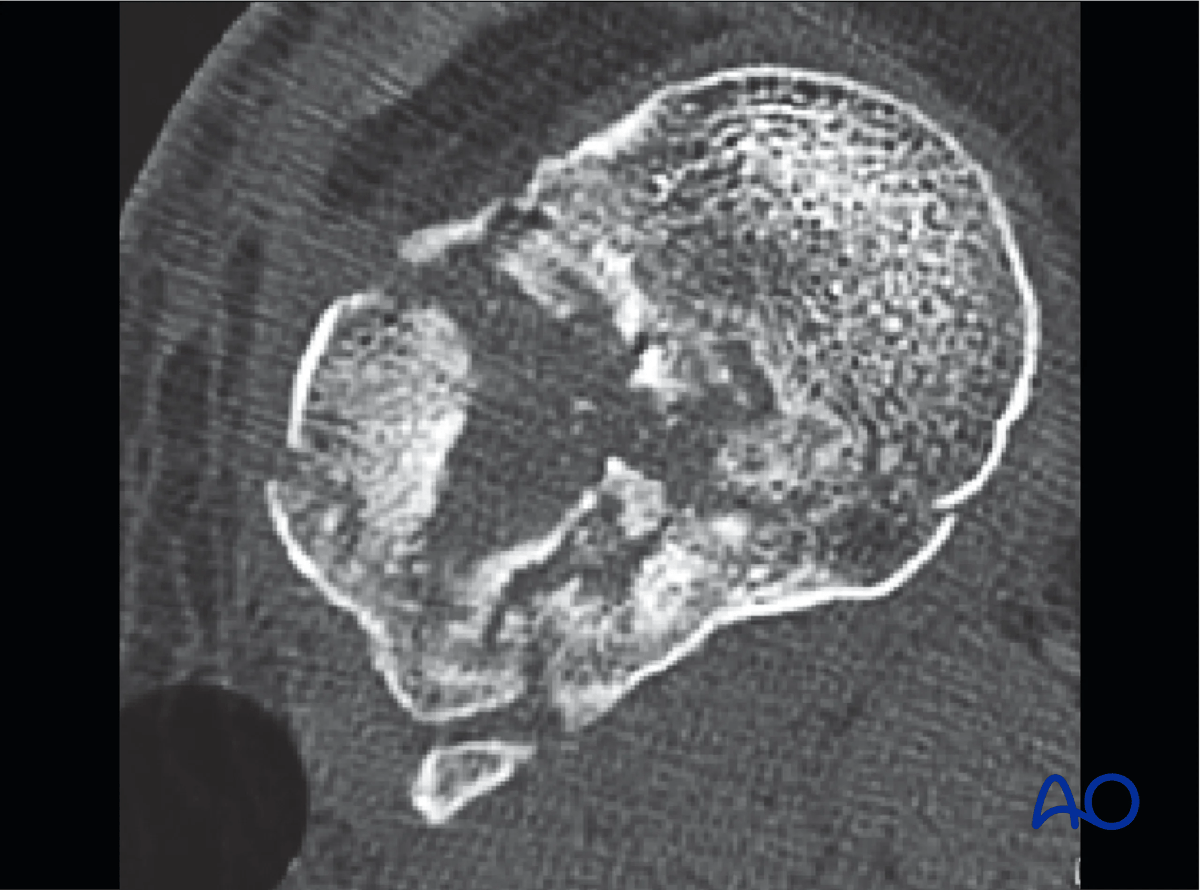

This image shows articular comminution and depression of the lateral tibial plateau. There is no transarticular medial plateau fracture.

Proximal tibia - articular comminution and depression of the lateral tibial plateau